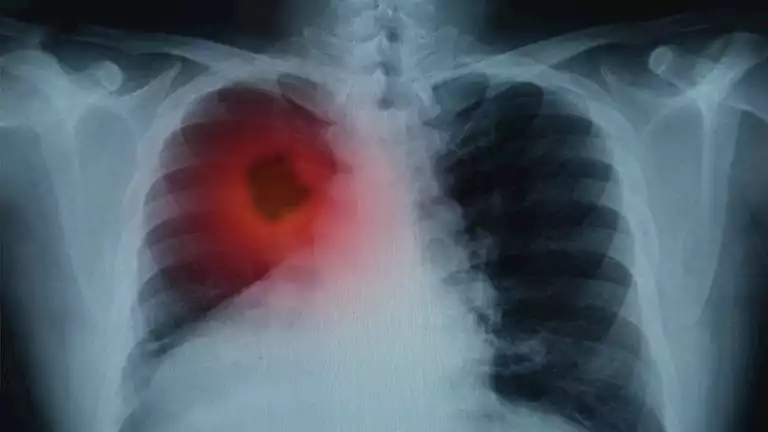

الرئتان من أهم الأعضاء في جسم الإنسان، فهما المسؤولتان عن إدخال الأكسجين الضروري للحياة والتخلص من ثاني أكسيد الكربون، ومع مرور الوقت، قد تتراكم في الرئتين...